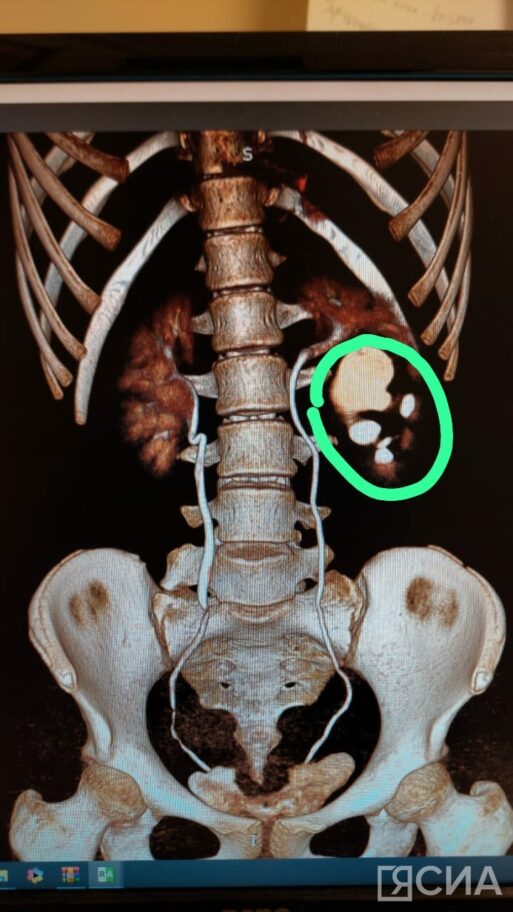

В Национальном центре медицины Якутии провели операцию по реконструкции мочеточника 9-летней пациентке с редкой врожденной аномалией. У девочки три почки – и все они теперь функционируют нормально. Об этом рассказал заведующий урологическим отделением Педиатрического центра РБ № 1 — НЦМ Сергей Купряков.

Подобная аномалия развивается внутриутробно и не вызывает неудобств человеку. По словам врача, пациентке выявили «полное удвоение почки», что является редкостью. Обычно при такой аномалии одна из половин удвоенной почки перестает функционировать, но в этом случае все было в норме. Врачи реконструировали суженный участок мочеточника.

«Такой случай полного удвоения встречается крайне редко. У ребенка по сути три почки: две из них функционировали с рождения нормально, а вот одна была с пороком – нарушением проходимости по мочеточнику. Мы восстановили эту проходимость малоинвазивным способом – лапароскопически, без крупного разреза. Участок мочеточника был суженным, за счет чего почка стала расширяться. Нам удалось иссечь этот суженный участок. Операцию провели совместно с детским урологом Морозовской детской клинической больницы Романом Суровым из Москвы», — рассказал Сергей Купряков.

«Операция была плановой. Удвоенная почка функционировала на 50%, она сдавливала второй сегмент. Без этой операции может произойти застой мочи в почке. Это вызывает воспаление, в последующем приводит к нагноению. У пациентки три почки и три мочеточника. Все функционируют нормально», — добавил Сергей Купряков.